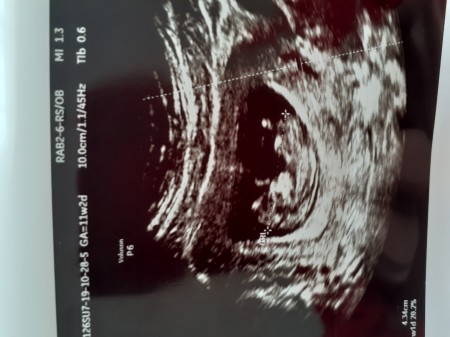

Merhaba değerli anneler ..

Bu benim bebegimin ultrason fotoğrafı..

Sizce kız mi erkek mi ???

11 +2

Kız diyorum öğrendiğinde bana söylermisin cinsiyetini içime kız dogdu

Rica ederim canım benim 9 haftalıken ki ultrasyon resmi var benimki erkek neden se seninki kız doğdu içime ve hayırlı sağlıklı olsun yeter bizimkisi merak sadece:)